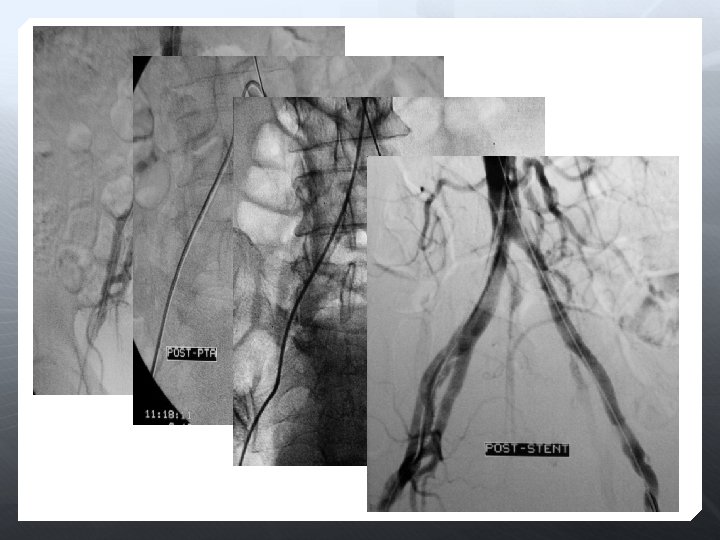

Yaşam tarzının modifikasyonu Endovasküler Sigara bırakma Düzenli egzersiz PTA (anjioplasti) Diet Stent-graft Plak debulking (perkutan aterektomi) Tromboliz (akut) Perkutan trombektomi (akut) İlaç tedavisi Antiplatelet tedavisi Risk faktörlerinin kontrolu ( hipertansiyon, kan şekeri) Statinler, beta-blokerler Cerrahi Endarterektomi Periferik bypass graft Amputasyon

PTA POBA Subintimal PTA Cutting Scoring DEB Stent Dedike olmayan Dedike BMS Nitinol Scaffold Stent-graft Aterektomi İlaç kaplı Balon Stent Lazer Tromboliz

PTA’ya yetersiz yanıt veya akımı engelleyen diseksiyon varlığında PTA’dan üstün olduğu bilinen damarlarda İlyak/subklaviyan a. oklüzyonlarında PTA’nın riskli olduğu alanlar